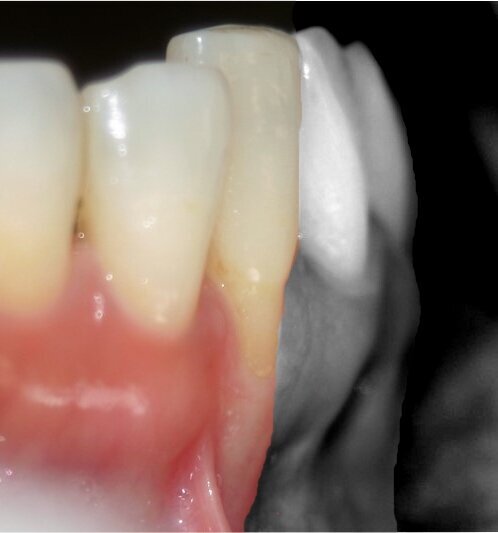

Fig. 3: Harvested Connective Tissue (CT) graft. An excess of adipose tissue in the graft leads to increased shrinkage.

For peri-implant soft tissue, a zone of keratinized tissue is known to provide better long-term stability (Fig. 4). However, from a soft tissue augmentation perspective, either for a tooth or an implant, the buccal positioning is critical when assessing the predictability of the surgical procedure at baseline. The more buccal the implant/tooth, the harder it generally is to graft around (Fig. 5).

Fig. 4: Good soft tissue maintenance around implants can be often obtained by soft tissue augmentation, thus improving tissue biotype and keratinization.